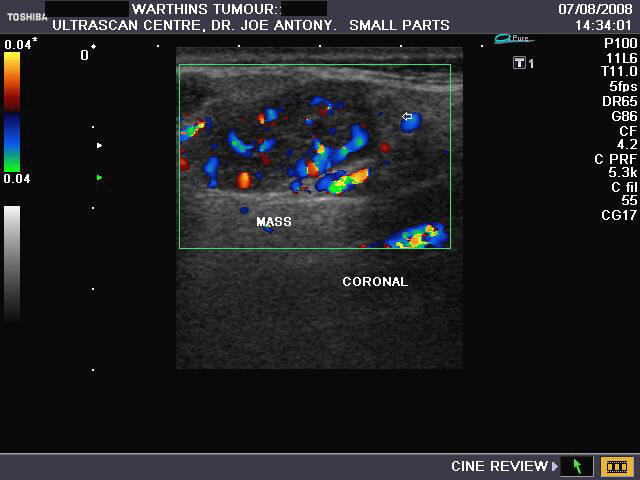

Warthin's tumour (cystadenolymphoma)

Sonography of salivary gland mass.

This 50 yr. old male patient complained of swelling and pain in the region of the parotid glands on both sides. Sonography of the parotid glands revealed 1) bilateral hypoechoic, well defined masses (larger on the right side) which show no significant acoustic enhancement. 2)The lesion in the right parotid measures 2.5 x 1.6 x 1.2 cms. and that on the left side measures 0.7 cms.3) Fine septae are seen within the masses. 4) Color doppler imaging shows multiple vessels within the mass with typical low velocity flow. These findings suggest either pleomorphic adenoma of the parotids or Warthin's timour. Absence of posterior acoustic enhancement in these ultrasound images suggests that this is a Warthin's tumour of the parotid gland. Histopathological study confirmed this to be Warthin's tumour.

Ultrasound images taken by Joe Antony, MD, using a Toshiba Nemio- XG color doppler machine.